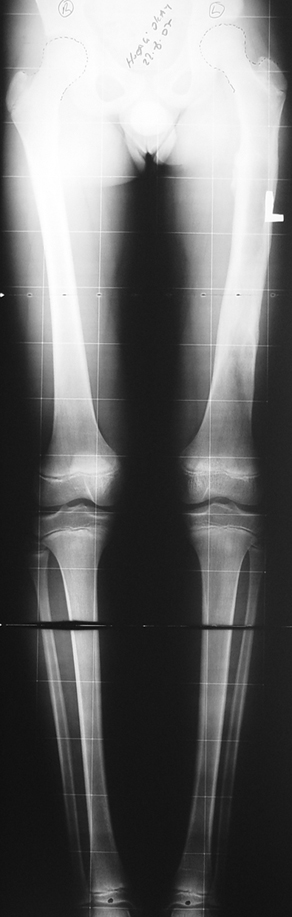

Uygun radikal debridman tüm nekrotik kemik ve yumuşak dokuların çıkartılmasını gerektirir, ve sıklıkla uzuvda instabiliteye neden olur. Kalan kemik ve yumuşak doku defektinin bir şekilde fiksasyonu ve rekonstrüksiyonu gereklidir. İlizarov’un ortaya koyduğu distraksiyon osteogenezi yöntemi, kaynamanın elde edilmesi, deformitenin düzeltilmesi, bacak boy eşitsizliğinin giderilmesi ve segmental defektlerin rekonstrükte edilmesi için başarıyla kullanılmaktadır.

Eksternal fiksatör ile geçen süre (eksternal fiksasyon indeksi), gereken distraksiyon miktarına bağlıdır ve bu süre boyunca bazı komplikasyonlarla karşılaşılabilir. Distraksiyon dönemi sona erdikten sonra, distraksiyon süresinin iki katını aşan konsolidasyon döneminde hastalar eksternal fiksatörü zorlukla tolere edebilirler. Yeterli konsolidasyon sağlanmadan eksternal fiksatör çıkartılırsa ise kırıklar, deformite ve kısalık oluşabilir. Hastanın fiksatör ile birlikte geçirdiği sürenin azaltılması ve böylece hasta konforunun ve aktivite düzeyinin arttırılması için intramedüller çivi üzerinden uzatma yöntemi uygulanmaktadır. Bu yöntemde distraksiyon dönemi sona erdiğinde kemiğin içindeki çivi statik olarak kilitlenmekte ve eksternal fiksatör çıkartılmaktadır. Stabilizasyon intramedüller çivi tarafından sağlandıktan sonra konsolidasyon dönemi gerçekleşmektedir. Bu şekilde hem eksternal fiksatörün uzun süre kalmasından hem de erken çıkartılmasından kaynaklanan komplikasyonların önüne geçilmektedir.